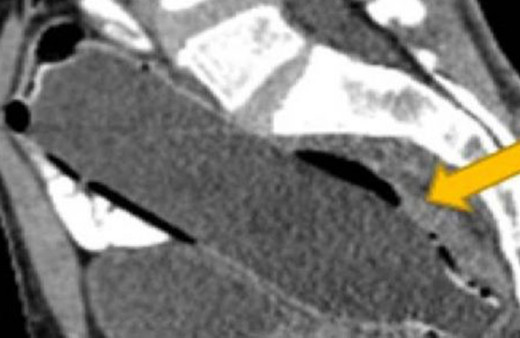

Makat